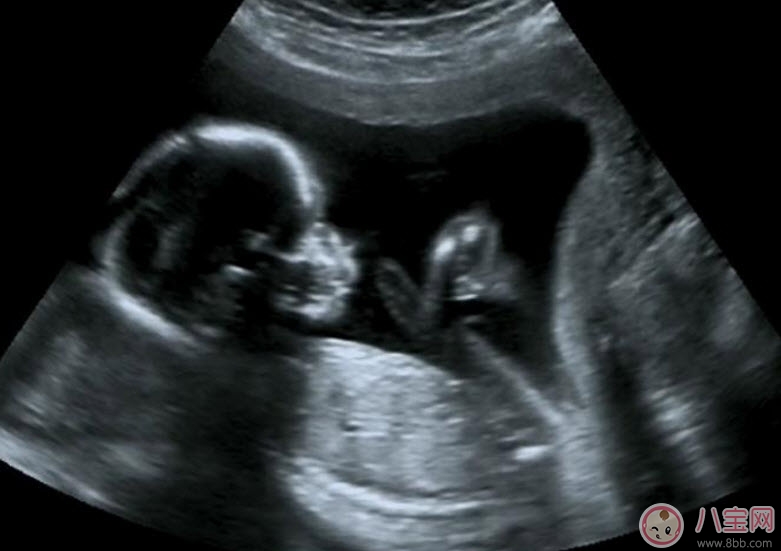

為監(jiān)測(cè)孕囊的部位、胎兒的生長(zhǎng)發(fā)育情況,降低畸形兒和有缺陷兒的出生率,早孕期陰道B超檢查顯然是很必要的。早孕期做陰道B超檢查有以下幾點(diǎn)好處:

1.清楚地了解孕囊的位置是否正常,明確是宮內(nèi)還是宮外妊娠(俗稱宮外孕)。

2.核實(shí)孕周、判斷胚胎發(fā)育情況。根據(jù)孕囊的平均直徑、胎芽大小、胎兒的頭臀長(zhǎng)判斷孕齡,有助于中晚孕期間判斷胎兒發(fā)育的狀況。經(jīng)陰道B超胎芽大于5mm時(shí),應(yīng)該見(jiàn)到胎心搏動(dòng)。如果沒(méi)有見(jiàn)到胎心搏動(dòng),提示有胚胎停止發(fā)育 的可能,應(yīng)定期復(fù)查。

3.判斷胚胎的數(shù)目,這是早期診斷是否多胎妊娠的最準(zhǔn)確的方法。

4.觀察胎盤的早期發(fā)育。妊娠6周時(shí),胚胎的葉狀絨毛膜與子宮的底蛻膜開始形成原始胎盤,妊娠8周,就可以辨認(rèn)出胎盤了。

5.及早發(fā)現(xiàn)子宮、附件的異常。了解是否有子宮畸形、肌瘤以及附件區(qū)腫物等等。